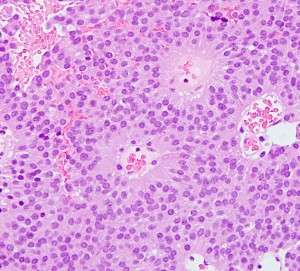

病理は良性です

WHO グレード1の良性腫瘍です。おとなしい性格です。左はもっとも多いびまん性タイプ diffuse typeです。円形で小型で均一な核が特徴です。細血管網のなかに腫瘍がシート状に広がります。

MIB-1染色率は3%以下です。それ以上のものはちょっと再発増大速度が速いかもしれません。

真の悪性下垂体腺腫は,0.2%(1000例に2例)くらいです。